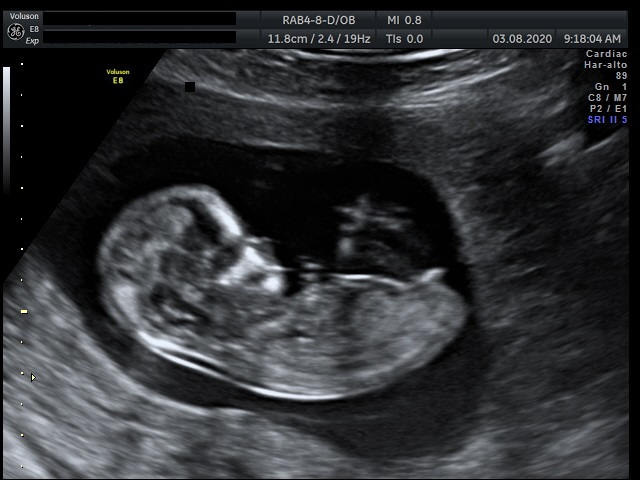

- Gravidanza e principali patologie ostetriche, Ecografie ostetriche, Patologia ginecologica, Ecografia ginecologica. Infertilità.

Foto e Video